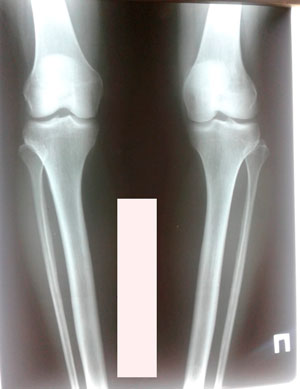

Исходник - 38 лет. Алматы.

Дата операции - 15.06.2019г.

Дата снятия аппаратов - 25.09.2019г.

Срок сращения - 100 дней.